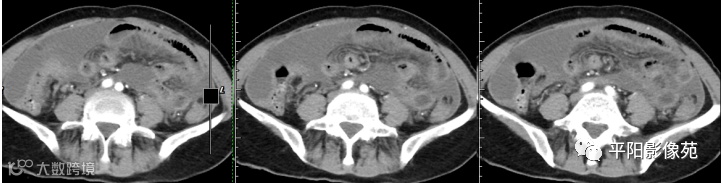

腹部增强 延迟期

壁腹膜增厚伴或不伴腹水;增厚的腹膜光滑、均匀,呈线带状,部分可见腹膜结节,网膜及肠系膜广泛浸润性改变;增强扫描明显强化。

合并淋巴结肿大,可钙化,若中心干酪样坏死,增强扫描环形强化